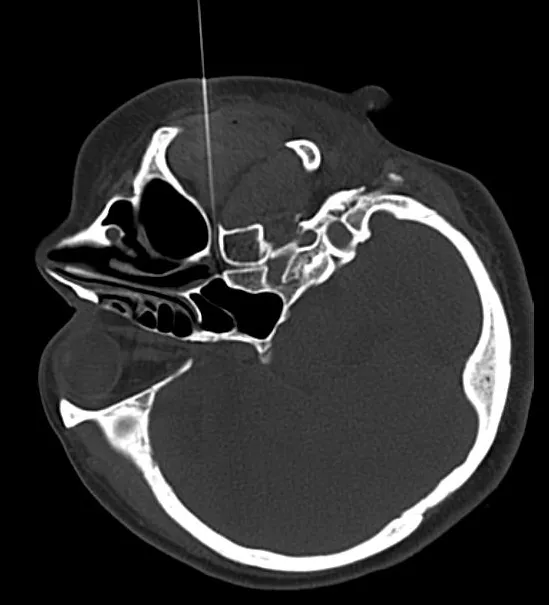

在CT引导下蝶腭神经节射频治疗,手术后有效率达95%以上。优势是: